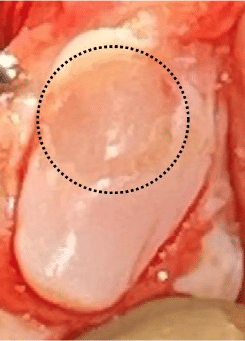

Despite the fact that the majority of dogs with patella luxation first have luxation when they are young, many owners will not notice clinical symptoms until later in life. This may be because the patella luxation starts out as being relatively infrequent. However, as the dog patella pops in and out of the groove it abrades the side of the groove (ie the ridge) and the cartilage on the patella. Over time, the cartilage gets worn down, both on the ridge and the patella. In fact, 66% of dogs who have patella luxation have full thickness cartilage wear lesions on their patella, ouch! As the ridge gets worn down, it becomes shorter and is less capable of preventing luxation of the patella and the patella luxation occurs more frequently.

The above photo shows a substantial loss of cartilage from the underside of the patella in a canine patient with patella luxation. Cartilage loss is common on both the dog’s patella and trochlear ridge.